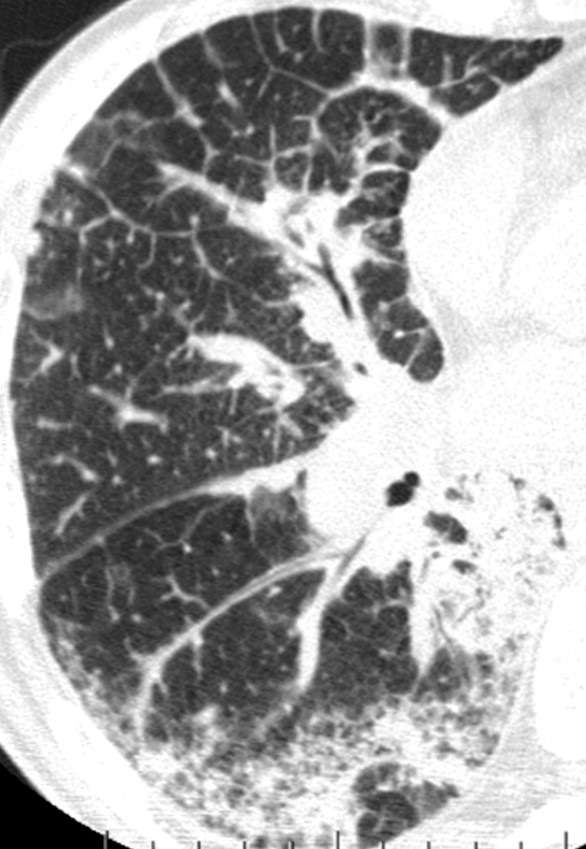

ALTERNATIVE DIAGNOSIS

The presence of any of these features should lead to the consideration of an alternative diagnosis.3,6

CT Features:

- Mosaic attenuation

- Predominant GGO

- Consolidation

- Cysts, nodules (profuse or centrilobular)

Predominant Distribution:

- Peribronchovascular

- Perilymphatic

- Upper or mid-lung

Other:

- Pleural plaques (consider asbestosis)

- Extensive lymph node enlargement

- Distal clavicular erosions (consider rheumatoid arthritis)

- Dilated esophagus, pleural effusions, pleural thickening (consider connective tissue disease)

Profuse perilymphatic micronodules

Image courtesy of and used with permission from David A Lynch, MD

Discrete cysts